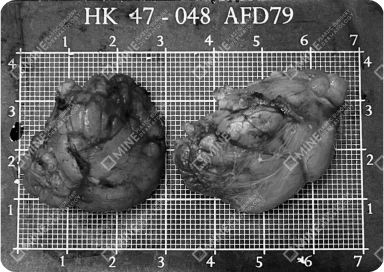

Check Removed Salivary Glands with Your Own Eyes

At MINE Plastic Surgery,

based on extensive experience in salivary gland removal procedures,

we show you the actual glands and fat tissues removed during surgery.

Symmetrical specimens laid out after successful salivary gland removal.

Medical grid used to measure gland size after salivary gland removal.

*Actual saliva gland that was removed from surgery patients at MINE.